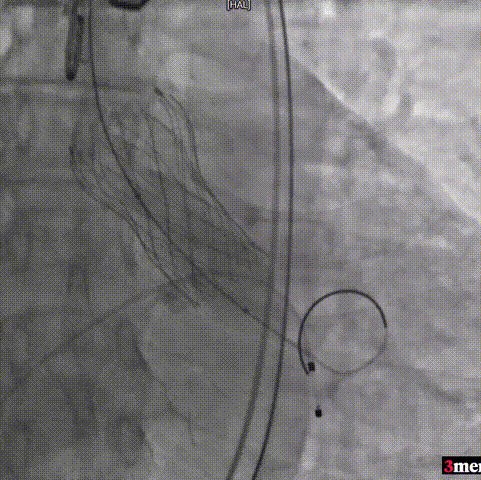

手术过程回顾:

患者全麻后,右侧股动脉建立主入路,主动脉根部造影显示主动脉瓣明显钙化。心室内轻微反流,主动脉及心脏情况整体较为稳定。直头导丝跨瓣后,在超硬导丝支撑下,瓣膜输送系统顺利跨瓣。在180次/分快速心室起搏下,确定降压至50mmHg后选择25mm球囊进行预扩张。根据术前评估及球囊预扩情况,最终选择直径29mm瓣膜进行植入。

主动脉根部造影

直头导丝跨瓣

球囊预扩

输送器过弓

输送器定位

瓣膜脱钩